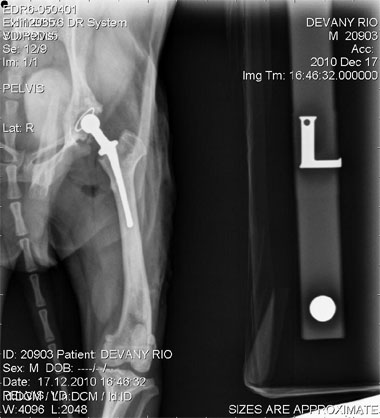

‘Nano’ total hip replacement in Yorkshire Terrier

June’s lecture will aim to explain current modalities of elbow, stifle and hip replacement in animals of all sizes from cats and small dogs to large dogs and make surgeons aware of the indications and implications of these to support discussion with clients.